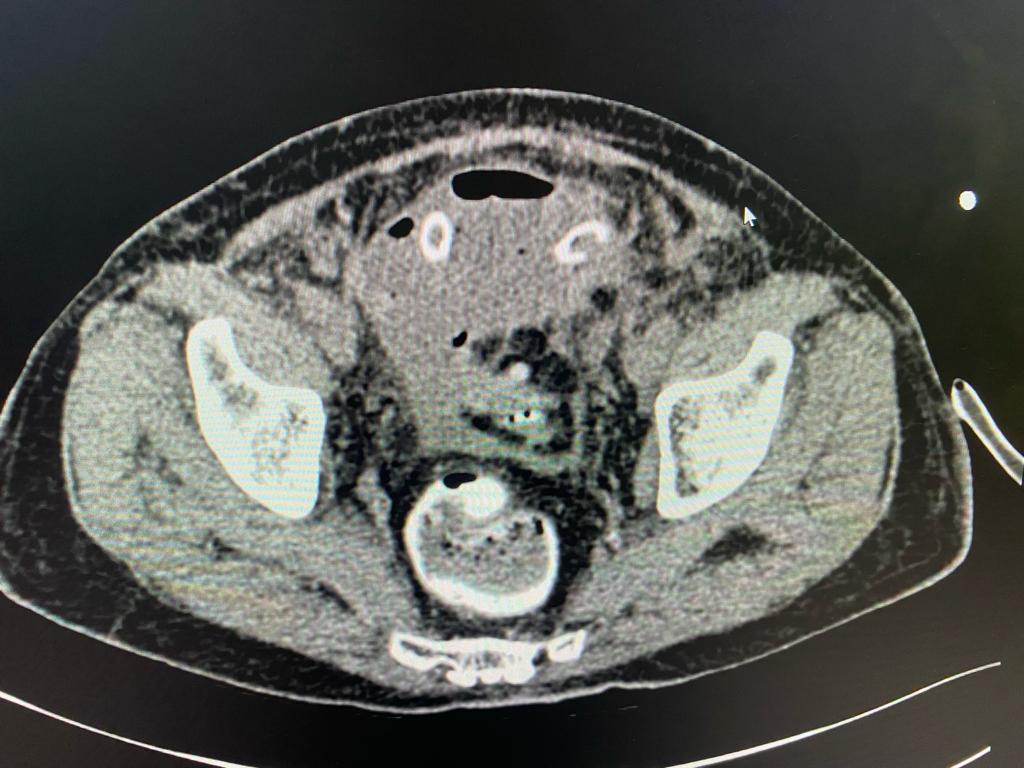

After admission, we reviewed the history, investigations, sequence of events and old CT scan. We suspected colonic diverticulosis with perforation as the original reason for sepsis. We repeated the CT scan of abdomen and pelvis which showed a pelvic abscess along with a sigmoid colonic diverticular phlegmon confirming diverticular perforation. The drain placed during previous laparoscopy was out of position. After a multidisciplinary meeting, treatment plan was charted out. The original drain was used to guide another drain deep in the pelvic abscess cavity under radiological guidance thus ensuring free drainage. The antibiotics were adjusted based on culture sensitivity of the intraabdominal pus. There were multiple highly resistant organisms and very few antibiotics were available for treatment. Hence the definitive surgery was deferred. Patient recovered and was sent home on intravenous antibiotics and drainage catheter.